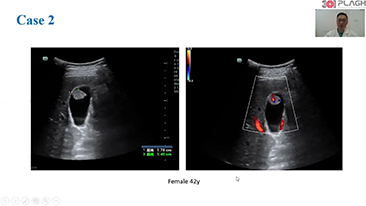

Algemene beeldvorming

Mindray Resona-oplossingen voor algemene beeldvorming helpen clinici bij het realiseren van nauwkeurigere en effici?ntere diagnose- en behandelingsresultaten door middel van sondes voor aparte toepassingen en effici?nte klinische toepassingstools.